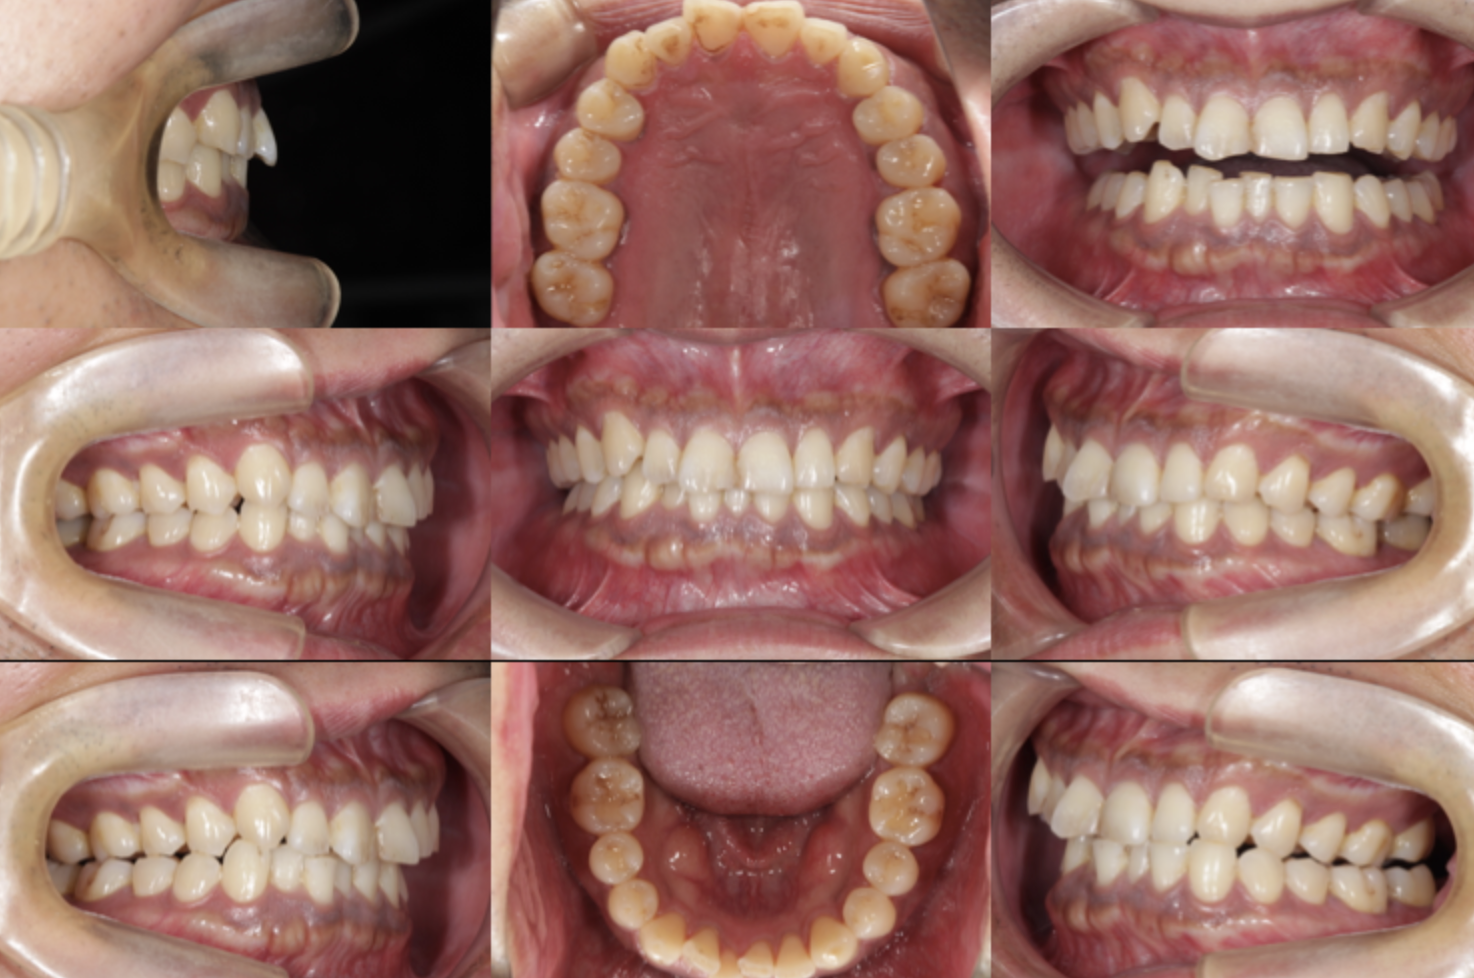

初診時、口腔内を確認すると、下顎前歯部に明らかな叢生を認めました。

治療は、右下2番の抜歯からスタートしました。

まず、抜歯スペースを活用して前歯のガタつきを徐々に整え、咬合平面が水平になるようコントロールしました。

治療後の変化:整然とした下顎前歯がもたらしたもの

実際、下顎前歯部の清掃性は格段に向上し、

歯ぐきの発赤(炎症)も改善。

歯列が整うことで唾液の流れも良くなり、自然の自浄作用が働くようになっていました。